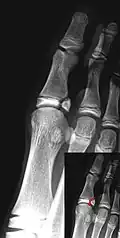

Salter–Harris fracture

A Salter–Harris fracture is a fracture that involves the epiphyseal plate (growth plate) of a bone, specifically the zone of provisional calcification.[2] It is thus a form of child bone fracture. It is a common injury found in children, occurring in 15% of childhood long bone fractures.[3] This type of fracture and its classification system is named for Robert B. Salter and William H. Harris who created and published this classification system in the Journal of Bone and Joint Surgery in 1963.[4]

There are nine types of Salter–Harris fractures; types I to V as described by Robert B. Salter and William H. Harris in 1963,[3] and the rarer types VI to IX which have been added subsequently:[5]

• Type I – transverse fracture through the growth plate (also referred to as the "physis"):[6] 6% incidence

• Type II – A fracture through the growth plate and the metaphysis, sparing the epiphysis:[7] 75% incidence, takes approximately 12-90 weeks or more in the spine to heal.[8]

• Type III – A fracture through growth plate and epiphysis, sparing the metaphysis:[9] 8% incidence

• Type IV – A fracture through all three elements of the bone, the growth plate, metaphysis, and epiphysis:[10] 10% incidence

• Type V – A compression fracture of the growth plate (resulting in a decrease in the perceived space between the epiphysis and metaphysis on x-ray):[11] 1% incidence